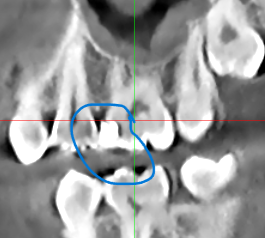

На 6 жевательном зубе справа на верхней челюсти в 2020 году поставлена пломба. Фото прилагаю. На КТ от 2024 года я сам нашел полость под пломбой, это вторичный кариес? Врач который смотрел КТ об этом не упоминал. Еще вопрос зуб же не депульпированный?

Все эти годы зуб не беспокоил. КТ скрины прилагаю.